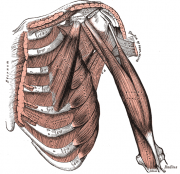

| 2021年7月26日 (一) 18:31 | Gray411.png (文件) |  |

69 KB | 77921020 | Uploaded with SimpleBatchUpload | 1 |